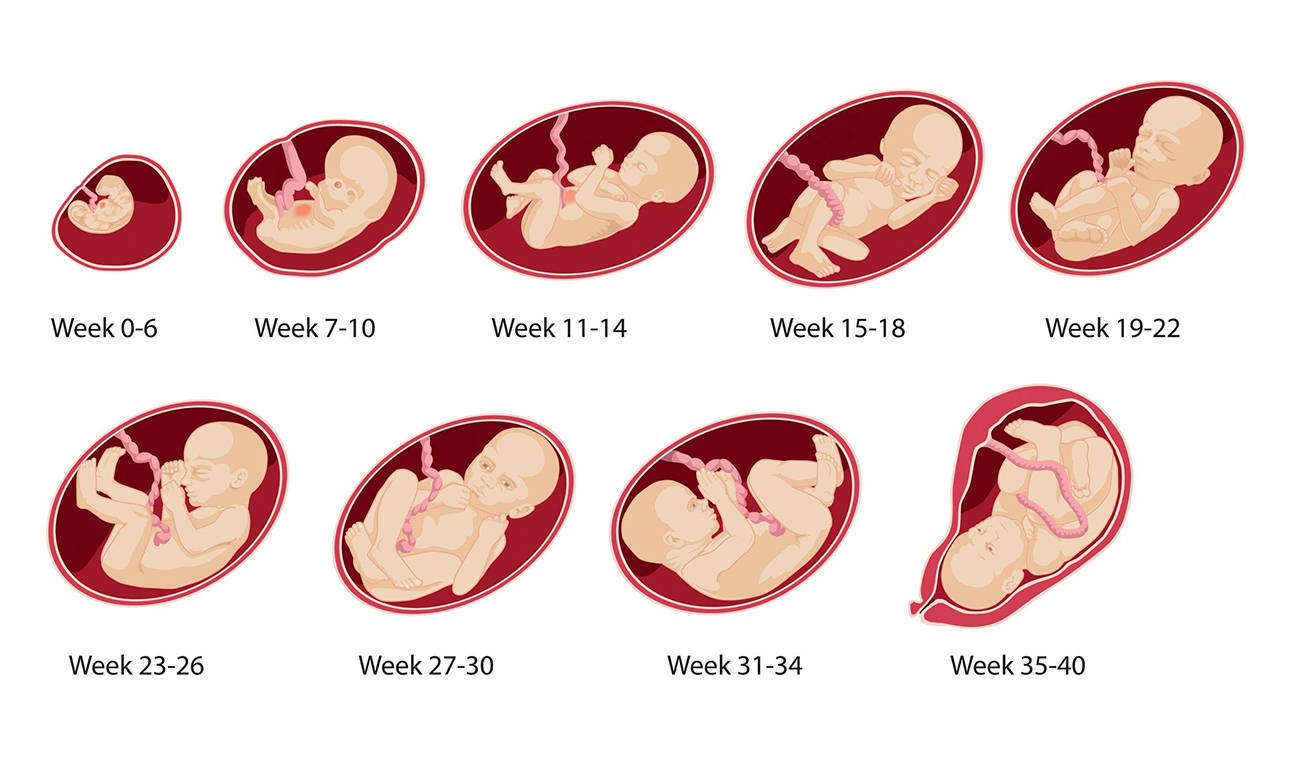

Формирование Плода в Первом Триместре: Важные Этапы